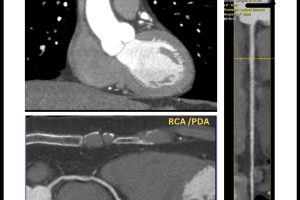

MSCT koronarografija je brza, precizna i neinvazivna metoda snimanja koja nam omogućava jasan uvid u stanje vaših koronarnih arterija. Pomoću najsavremenije CT tehnologije, možemo detaljno analizirati protok krvi i identificirati eventualna suženja ili blokade.

3. Precizna dijagnostika: Najsavremenija tehnologija omogućuje nam otkrivanje čak i najmanjih promjena u koronarnim arterijama.